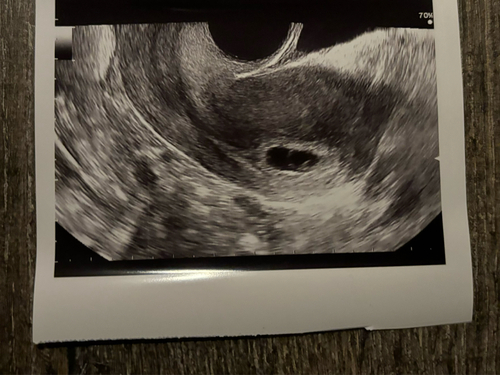

Ik ben zelf gisteren met 7+4 geweest en hetzelfde bericht gekregen. Mijn wereld stortte in. Het was te klein voor mijn termijn en er was geen kloppend hartje. Ik weet het exact doordat mijn eisprong dmv fertiliteitstraject is gemonitord. Bij mag zag het er als volgt uit. Ze heeft niets over een termijn gezegd, maar als ik ze vergelijk lijken onze foto’s redelijk op elkaar. Ik moet as woensdag weer terug. Ze was bij ons redelijk duidelijk en gaf geen hoop op verbetering.